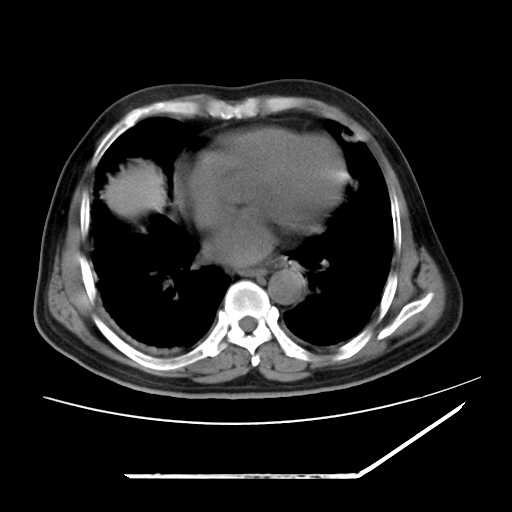

男,57,畏寒,发热

两肺野多发大小不一高密度灶,纵膈内见肿大淋巴结,要考虑转移瘤可能。双侧胸腔少量积液。

双肺多发结节样病灶,部分内见透光区,纵隔内见淋巴结肿大。结核临床如有畏寒,高热,白细胞增高首先考虑迁徙性肺脓肿(多是金黄色葡萄球菌感染)。

注意除外转移瘤。

1)考虑两肺感染性病变(金黄色葡萄球菌肺炎?);建议抗炎治疗后复查排除其他。2)双侧少量胸腔积液。